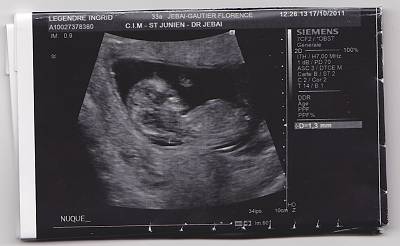

besoin d aide qui si connait en echo fille ou garcon

bonjour j au rais souhaiter savoir si vous connaissez en echo pouvez vous me donner votre avis merci fille ou garcon

posté par ingrid1523 le 24-11-2011 à 08:15

je vous mets une autre